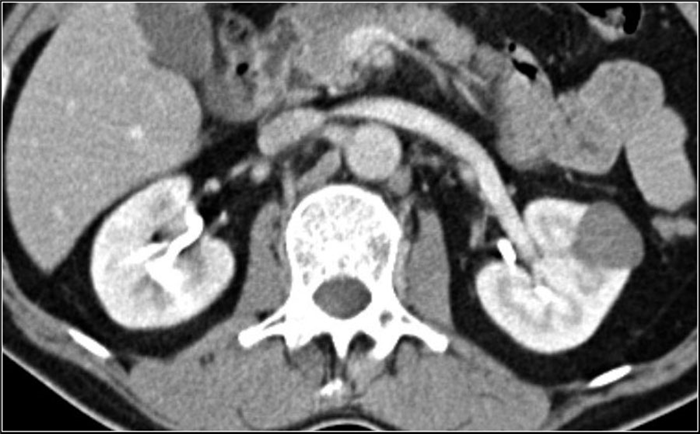

(Справа) КТ с контрастированием, аксиальная проекция: у мужчины 47 лет с остро возникшей болью в правом боку после мотоциклетной аварии выявлен травматический инфаркт правой почки вследствие тупой травмы. (Слева) КТ с контрастированием, аксиальная проекция: у мужчины 38 лет, получившего тупую травму из-за автокатастрофы, выявлен обширный инфаркт почки с отсутствием контрастирования. Обратите внимание на слабое контрастирование кортикального ободка.